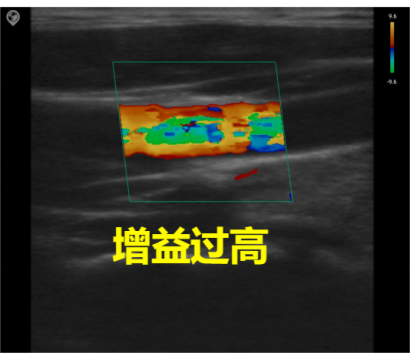

Common parameter adjustment for C mode

Gain

Total gain: Adjusts the sensitivity of blood flow signals, with the gain value displayed in real-time on the image parameter area of the screen.

Image quality: Excessive gain obscures the image with chaotic color spots, while insufficient gain may lead to loss of blood flow signals. During actual adjustment, the optimal setting is to clearly distinguish red and blue blood flow without color aliasing.